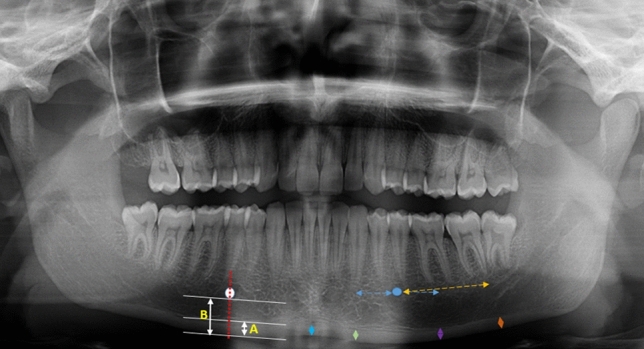

The morphometric measurement has been carried out using Planmeca Romexis 4.6.2.R software (PLANMECA Romexis, Helsinki, Finland). The cortical thickness measurements were carried out on panoramic radiography as performed on cone-beam computed tomography (CBCT) by Barra et al. [18]. Accordingly, radiomorphometric indices were measured on symphysis, anterior, molar, and posterior regions of the in right and left side of jaws and the mean of both measurements was represented as the mean value. The symphysis index (SI) was measured perpendicular to the inferior mandibular cortex, equidistant from the right and left mental foramen centers. Anterior index (AI) was measured perpendicular to the inferior cortex of the mandible, 1 cm in front of the mental foramen, parallel to the long axis of the mandible. The molar index (MI) was measured 1 cm behind the mental foramen, parallel to the long axis of the mandible, and perpendicular to the inferior cortex of the mandible. And the posterior index (PI) was measured 2.5 cm behind the mental foramen, parallel to the long axis of the mandible, and perpendicular to the inferior cortex of the mandible (Fig. 2) [18].

Fig. 2.

Panoramic mandibular index measurement in the right mandible (PMI = A/B), mandibular cortical thickness measurement in the left mandible from anterior to posterior respectively; symphysis index (blue arrow), anterior index (green arrow), molar index (purple arrow), posterior index (orange arrow)

The PMI is the ratio of the distance between the mandibular cortical width (MCW; it is a line perpendicular to the inferior border of the mandible at the center of the mental foramen) by the distance between the inferior border of the mental foramen and the inferior mandibular cortex (Fig. 2). The reason for choosing the mental foramen area is that there are no masticatory muscles attached to this area [19]. The average of two different measurements for the right and the left side represents the mean value of the PMI.